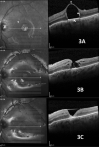

Background: To draw comparisons between spectral domain optic coherence tomography (SD-OCT) features of subretinal silicon oil (SO), perfluoro-n-octane (PFO) or C3F8 gas.

Methods: Cases diagnosed with retained subretinal vitreous substitutes (VS) were retrospectively selected. Demographic data were collected and OCT features were analyzed.

Results: In the 13 cases with subretinal PFO, hyper-reflectivity under the bubble was noted in 8 eyes (61.5%); choroidal shadow at the borders of the bubble in 11 eyes (84.6%); hyper-reflective halo around the bubble in 5 eyes (38.4%) and a hyper-reflective apical dot in 8 eyes (61.5%).The two cases with multiple PFO bubbles had complete septum dividing the bubbles. The one case with subretinal SO had hyper reflectivity under the bubble; no choroidal shadow at the edge of the bubble; hyper-reflective halo was noted around the bubble and the apical hyper-reflective dot was present; there was no complete septum dividing multiple bubbles. The single case with subretinal C3F8 had some bubbles with totally round base, incomplete septum, hyper reflectivity under the bubble, choroidal shadow at the edge of the bubble, a hyper-reflective halo and an apical dot.

Conclusion: Different subretinal VS share similar SD-OCT characteristics. Round base bubbles are only observed with subretinal C3F8 gas, while incomplete septum are related to retained subretinal SO or gas.